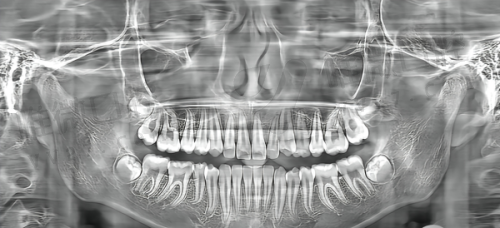

珠海九龙口腔自2009年成立以来,在本地声誉颇高,是少有的独栋牙科医疗大楼。医院配备CBCT影像系统、数字导板种植等精良设备,医生团队多来自香港、广州三等级医院体系进修,有丰富的前牙即刻修复、后牙复杂骨增量手术经验。

该门诊隶属于国内外连锁品牌,是瑞典诺贝尔指定种植中 心之一。专攻高端种植体系,如瑞士士卓曼、瑞典Nobel、德国Camlog等,手术采用微创导板术式,术后修复快且美观度高。